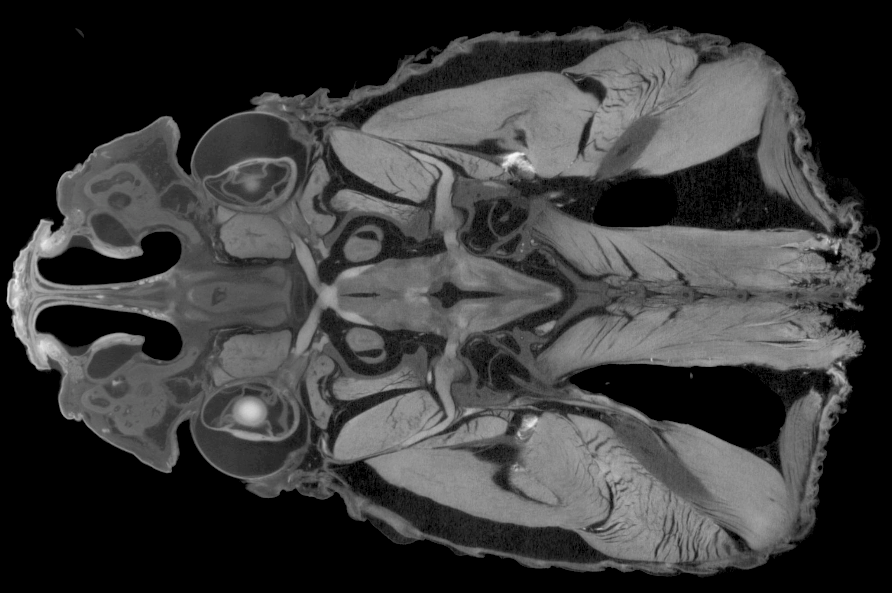

Welcome to the online home of Diffusible Iodine-based Contrast-enhanced Computed Tomography.

Our mission is to provide digital resources for the diceCT community and to connect interested researchers with contrast-enhanced imaging veterans. Watch this space and @diceCT for updates on new publications, tips & tricks, and diceCT-related events.